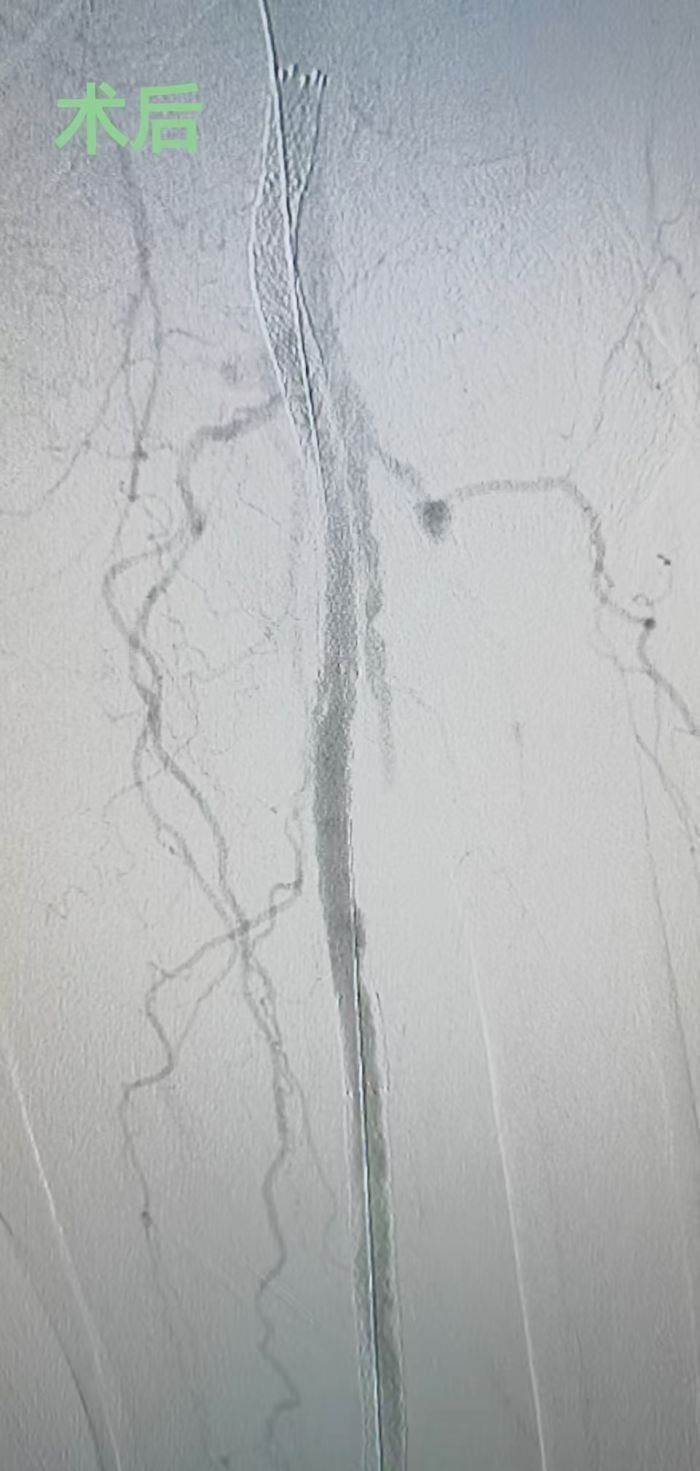

1月9日,中南大学湘雅二医院桂林医院血管外科团队成功为一名82岁的下肢动脉硬化闭塞症患者实施下肢动脉支架内再闭塞疏通手术,术中采用了广西首台装配的Excimer Lacer准分子激光系统,成功开通患者闭塞的股腘动脉支架,为后续治疗创造了有利条件。该手术标志着血管外科在复杂下肢动脉闭塞治疗领域达到了新的技术高度。

李鑫主任介绍,TurboElite准分子激光导管是目前国际上最先进的血管减容设备之一,能够通过激光能量精准消融血管内的堵塞物质,尤其适用传统方法难以处理的复杂闭塞病变和支架内再闭塞病变。手术耗时不到两个小时,患者长达30厘米的闭塞支架被重新贯通,辅助药物球囊扩张后,闭塞段血流速度恢复正常。